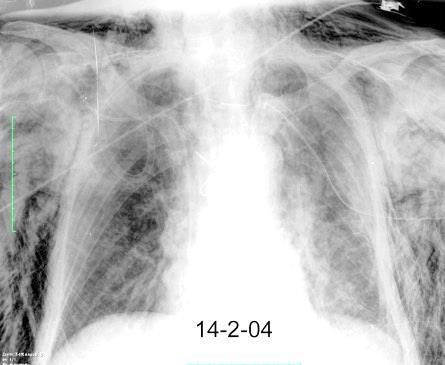

Masa axilar izquierda y derrame pleural derecho. Implantes pleurales, paraespinales . Ganglios en mamaria interna. Linfoma B difuso

Pliegue axilar Normal

Rehúsa cirugía

2011. Acude por masa axilar

Linfoma NH de cél. B. Invasión Transtorácica.

Afectación axilar